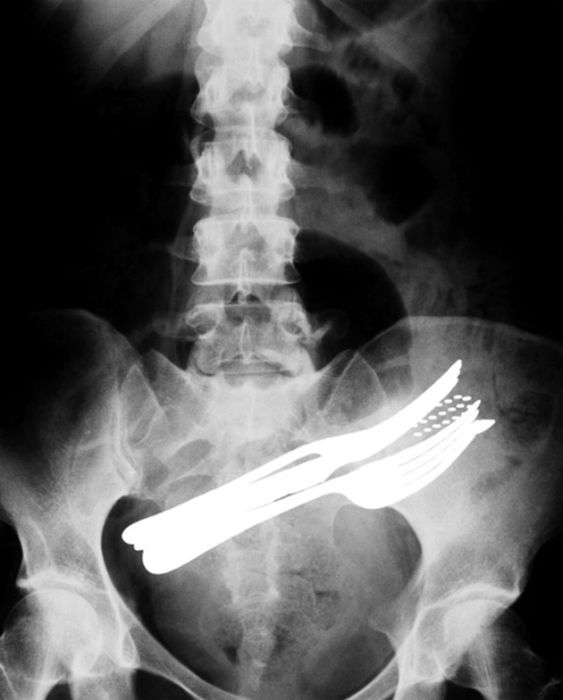

Рентгеновские снимки людей, которые умудрились сами или с чужой помощью разместить внутри своего организма разные посторонние предметы. От вилок и ножей до пуль и бензопилы (!!!). По этическим соображениям обычные снимки таких травм и повреждений выкладывать нельзя, зато рентгеновские можно – на них травмы видны достаточно условно, хоть и очень понятно.